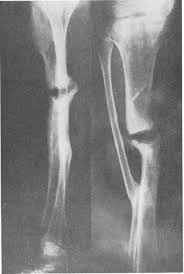

Cortaba el hueso, ajustaba los aros y los radios y fijaba la extremidad, de manera que no hacía falta enyesar al paciente. Transportaba poco a poco la extremidad, evitando lesión nerviosa, y en un segundo tiempo llenaba el defecto de injerto óseo.

La distracción ósea se basa en romper el hueso conservando la circulación sanguínea, y distraerlo, formándose hueso nuevo en el hematoma de fractura.